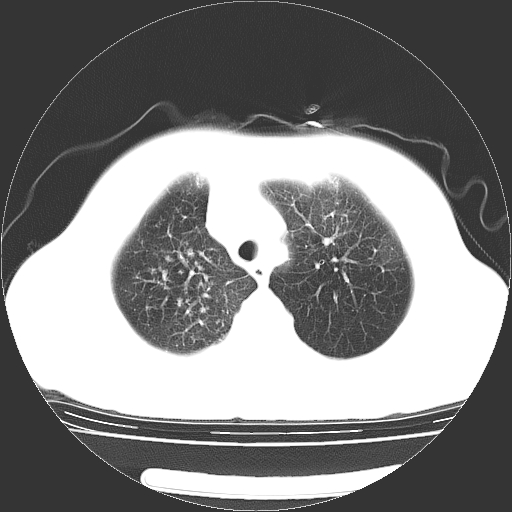

标题: CT23067:女,70岁,咳嗽、咳痰一个月,低热一周。 [打印本页]

女,70岁,咳嗽、咳痰一个月,低热一周。

1.左上肺结核,部分纤维化。右肺中下叶部分肺不张,内见液化、坏死及点状钙化,右中下叶支气管壁增厚、管腔狭窄,见多个点状钙化,结合临床考虑支气管内膜结核,建议痰检查抗酸杆菌并参考血沉。两肺多个小圆点状高密度灶,境界模糊,多考虑结核肺内播散。但本人年龄较大首先应支气管镜检以除外右肺癌。

2.胸主动脉夹层。

一元论:内膜结核伴下肺阻塞性肺炎并双肺播散!另:主动脉夹层。右侧少量胸腔积液。